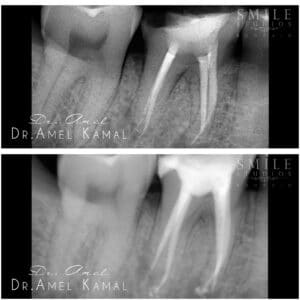

-The visit starts by taking Xrays to the tooth, applying Local anesthetic agents to carry out the procedure completely painlessly.

The procedure of the root canal treatment is always done painlessly, as we start by numbing the area of the referred tooth, and starting to clean the decay or fractured part of the tooth, reaching out to the tooth pulp/ or the root canals as they are known of. followed by disinfecting them and filling them back to prevent any further reaccumulation of micro/organisms into the canals.

-Once the Root canal treatment is done, the tooth is restored back with a cosmetic dental filling unless a crown, inlay, or an inlay ( which are most of the cases needed to restore the previously lost tooth structure leading to the root canal treatment ).